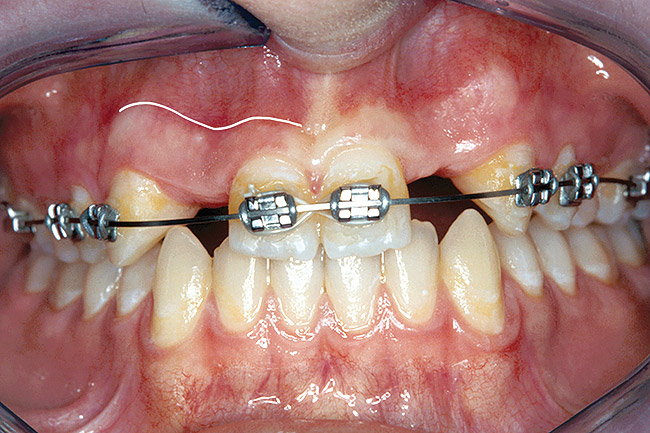

Figure 26  VIRTUAL PLANNING AND SURGERY Before implant surgery, the orthodontic brackets were removed, revealing the position of the centrals, and the anatomical variations of the crestal tissue and lack of interdental papilla.

Figure 26

Figure 27   VIRTUAL PLANNING AND SURGERY Before implant surgery, the orthodontic brackets were removed, revealing the position of the centrals, and the anatomical variations of the crestal tissue and lack of interdental papilla.

Figure 27

Figure 28   VIRTUAL PLANNING AND SURGERY Before implant surgery, the orthodontic brackets were removed, revealing the position of the centrals, and the anatomical variations of the crestal tissue and lack of interdental papilla.

Figure 28

Before the day of surgery, the patient was seen by the orthodontist for the removal of the orthodontic brackets. The patient still was not pleased with the position of the two centrals, and it was determined that this would be addressed after implant placement (Figure 26). The anatomical variations of the crestal tissue and lack of interdental papilla can be appreciated in the close-up views of the right and left sites (Figure 27 and Figure 28). There were no surprises on the day of surgery as all of the decisions were made during the planning phase, before the scalpel ever touched the patient. The occlusal view of the CT 3D model revealed the wider alveolar ridge on the right side and thinner crest on the left side (Figure 29). This was confirmed when the full-thickness mucoperiosteal flaps were elevated, and the underlying bone revealed (Figure 30). The tooth-borne templates were designed to facilitate the drills and drilling sequence specific to the diameters of the predetermined implants (Figure 31). Each template contained an embedded 5-mm long stainless steel tube, which was approximately 0.2-mm wider than each drill (just wide enough to allow for the drills to rotate freely). Once positioned over the natural teeth, the template was secure and offered precision accuracy in transferring the implant locations from the original software-designed plan, allowing the potential for internal and external irrigation (Figure 32).